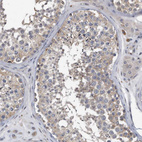

Immunohistochemical staining of human cerebral cortex shows strong positivity in neuropil.